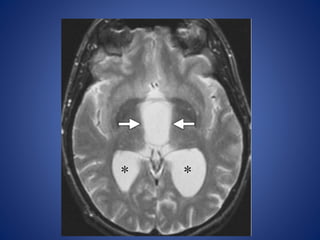

• #24 Suprasellar arachnoid cyst. (a) Midline sagittal T1WI shows a cyst (arrows) that is isointense relative to cerebrospinal fluid.

• #25 (b) Axial T2WI, the cyst (arrows) is homogeneous and isointense relative to cerebrospinal fluid. The lateral ventricles (*) are dilated due to obstruction by the cyst.

• #26 the cyst (arrows) demonstrates no enhancement